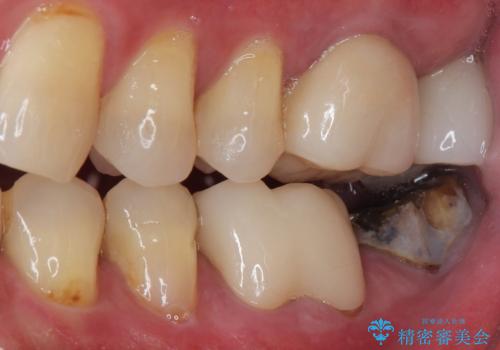

- 左下の奥歯の被せものが外れ、噛むと痛みがあると来院された患者様です。

歯根破折の疑いがあり、顕微鏡下で染色して確認したところ破折線は認められませんでした。

そのため再根管治療の適応と判断し、治療を進めていくこととしました。